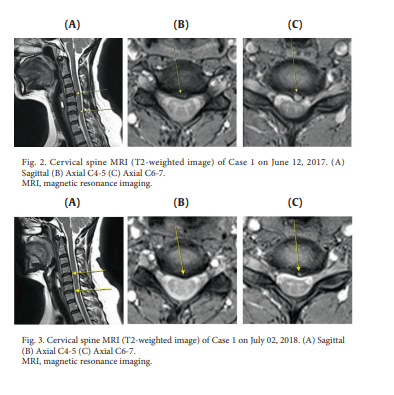

아래의 논문은 목허리 디스크에 도침치료는 경항통과 요통의 개선은 물론 MRI상에서 탈출한 수핵의 재흡수를 확인한 연구입니다

이 연구의 목적은 침도치료에 따른 허리디스크 탈출 수핵의 재흡수에 관한 보고였습니다.

두 명의 환자가 경추 또는 요추 추간판탈출증에 대한 통합적인 한약 치료를 포함하는 침도치료를 받았습니다. 자기공명영상(Magnetic Resonance Imaging)은 치료 전후의 영상을 생성하기 위해 사용되었고, 입원 및 퇴원 시 환자를 평가하는 데 사용되는 수치 등급 척도 점수 및 운동 범위를 체크하였습니다. 두 경우 모두 자기 공명 영상에서 각각의 허리 디스크의 상당한 재흡수가 관찰되었고, 수치 등급 척도 점수가 감소했습니다. 동작 범위가 1건에서 개선되었습니다. 이 연구는 침도 치료가 탈핵성 허리디스크의 디스크재흡수 및 통증 완화에 효과적인 치료법일 수 있다는 것을 보여줍니다.

*도침치료후 재흡수된 디스크, 디스크에 침도 치료효과를 명확히 보여줍니다